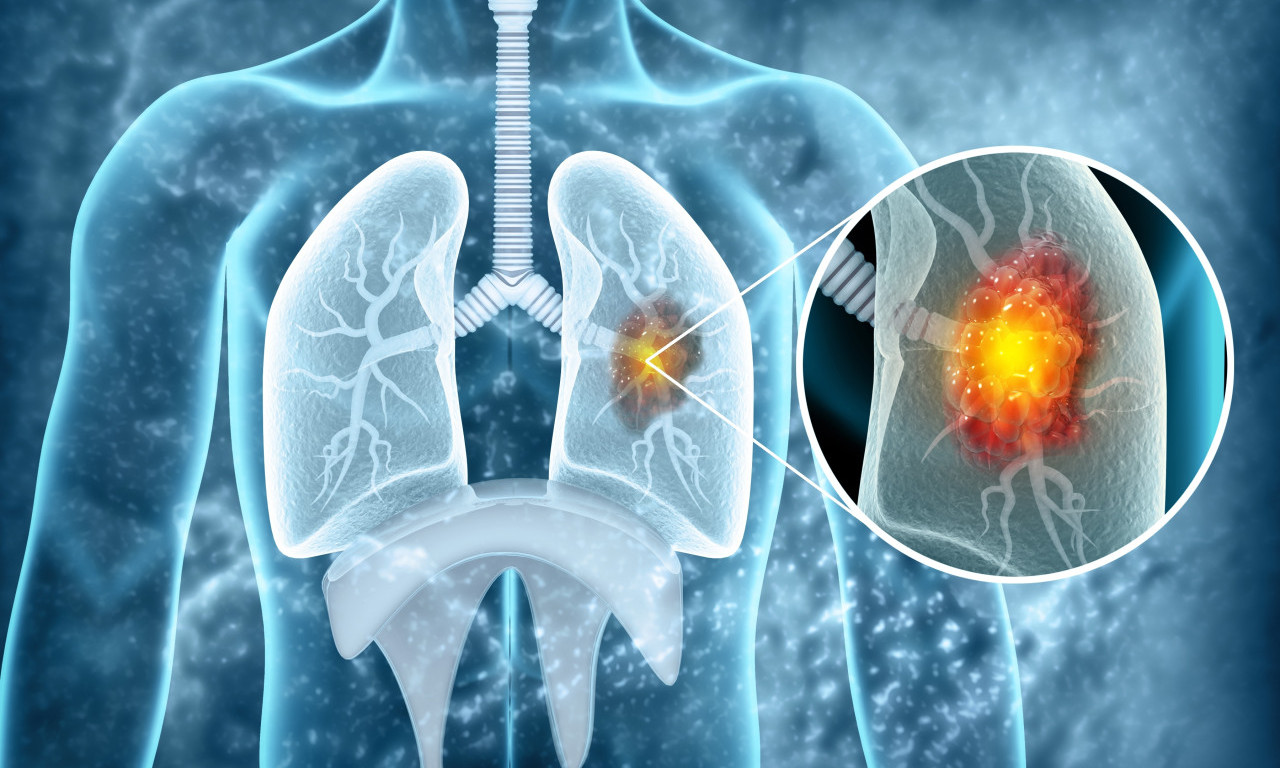

rak pluća

VEŠTAČKA INTELIGENCIJA OTKRIVA RAK PLUĆA MESEC DANA UNAPRED! Potrebno je uraditi osnovne medicinske analize

Na svaka dva sata u Srbiji jedna osoba premine od KARCINOMA PLUĆA! Od jeseni počinje "borba" u SRBIJI, a evo i kako

Svetski dan borbe protiv raka pluća obeležava se svake godine 1. avgusta.

Rak pluća je vodeći uzrok smrti od raka u svetu, a godišnje ima 1,8 miliona smrtnih slučajeva od kancera pluća